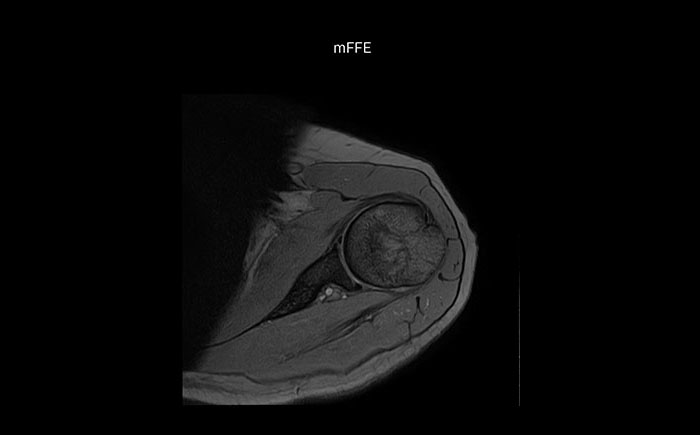

Shoulder MRI with high quality, large coverage

The Prodiva shoulder coil is very flexible and has large coverage, which makes good positioning easier, and that contributes to the superb image quality and high SNR that we get in our shoulder exams.

Scan time 2:55 min, FOV 160 mm, acq voxels 0.55 x 0.83 x 3.0 mm.

Scan time 4:19 min, FOV 160 mm, acq voxels 0.55 x 0.80 x 3.0 mm.

Scan time 2:50 min, FOV 160 mm, acq voxels 0.70 x 0.99 x 3.0 mm.

Shoulder MRI with high quality, large coverage

The Prodiva shoulder coil is very flexible and has large coverage, which makes good positioning easier, and that contributes to the superb image quality and high SNR that we get in our shoulder exams.

Scan time 2:55 min, FOV 160 mm, acq voxels 0.55 x 0.83 x 3.0 mm.

Scan time 4:19 min, FOV 160 mm, acq voxels 0.55 x 0.80 x 3.0 mm.

Scan time 2:50 min, FOV 160 mm, acq voxels 0.70 x 0.99 x 3.0 mm.